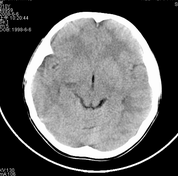

男,10岁,因近来常头痛就诊。先平扫拟诊右侧脉络膜裂囊肿,后薄层(3mm)扫描见此灶与右侧脑室后角相通,且向内几乎与鞍上池相连,并见一血管影沿其走形 (可能是脉络膜前动脉)。1。请教:脉络膜裂或脉络膜裂囊肿与侧脑室颞角或鞍上池相通吗?好像谁说脉络膜裂是脉络膜从外侧裂向侧脑室移行的裂隙。请高手讲讲这点的解剖关系。2。建议:对于老年患者,有丘脑附近特别是右丘脑附近的近似腔隙性梗死灶,临床症状不明显的,应做3mm薄层扫描,看病灶向下是否与侧脑室颞角相连,以免误诊。

薄层强化: